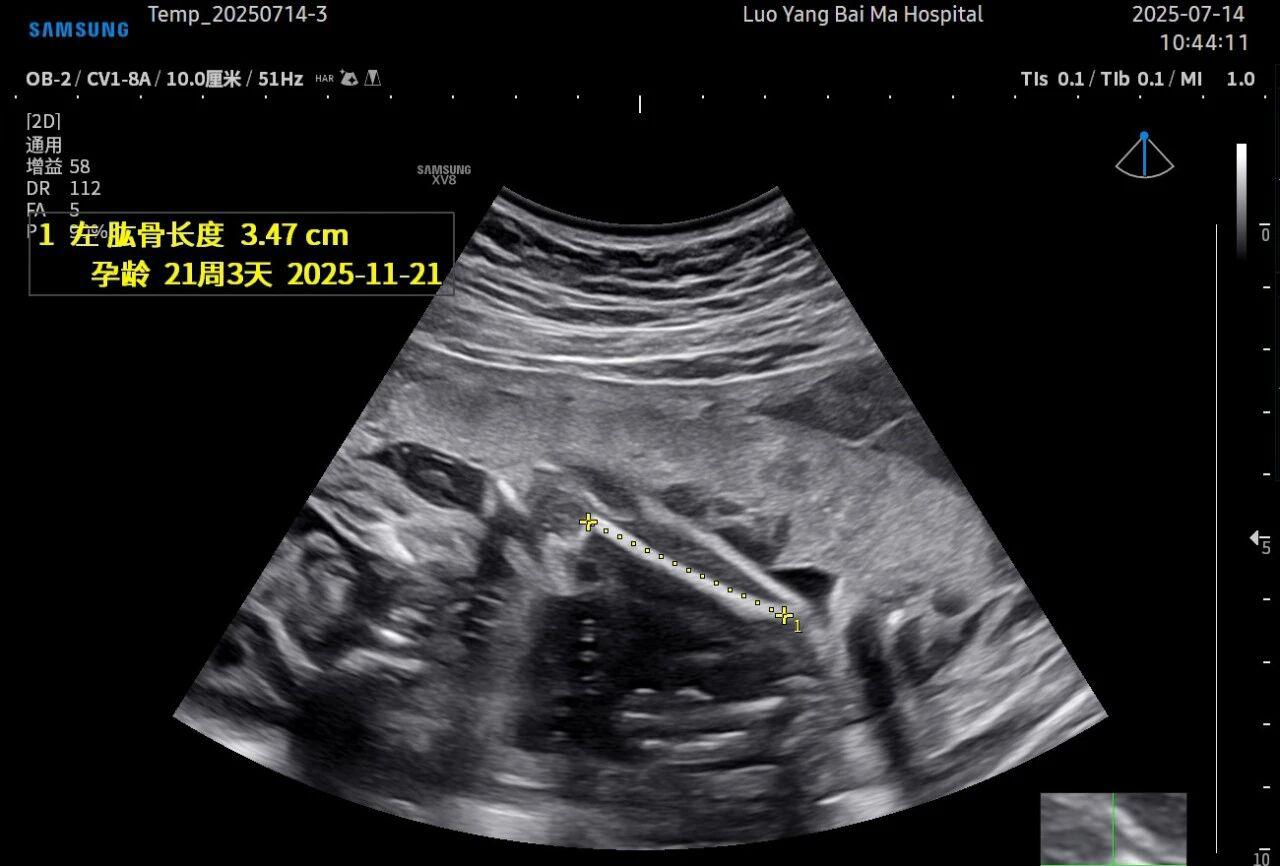

孕中期(通常在22-28周)的大排畸检查是整个孕期至关重要的环节之一。其目的在于系统地筛查胎儿是否存在结构性异常,如唇裂、脊柱裂、大脑、心脏、骨骼发育不良等问题。在这一关键检查中,5D智能彩超凭借其技术特性,展现出了显著的优势。

这是5D技术的核心优势之一。系统内置了强大的智能化大数据分析功能和AI辅助诊断工具。例如,在进行胎儿颈项透明层(NT)测量、胎儿长骨(LB)测量等关键生物学指标评估时,5D智能系统可以自动识别解剖层面、智能勾勒测量范围并进行计算。这不仅大大缩短了检查时间,更重要的是,它通过标准化的智能算法减少了因人为操作可能产生的误差,使诊断结果更加客观、可靠。